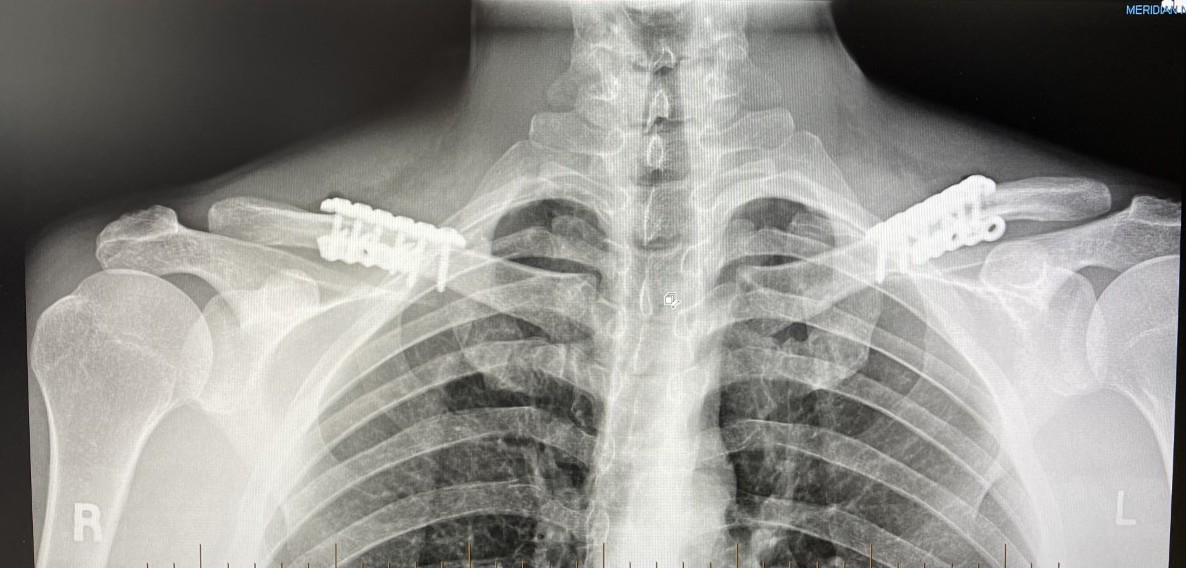

shoulder reduction postop x ray Dr Barry Eppley

The Surgical Technique of Clavicular Osteotomies in Shoulder Width Reduction

Shoulder width reduction is done by shortening the length of the...